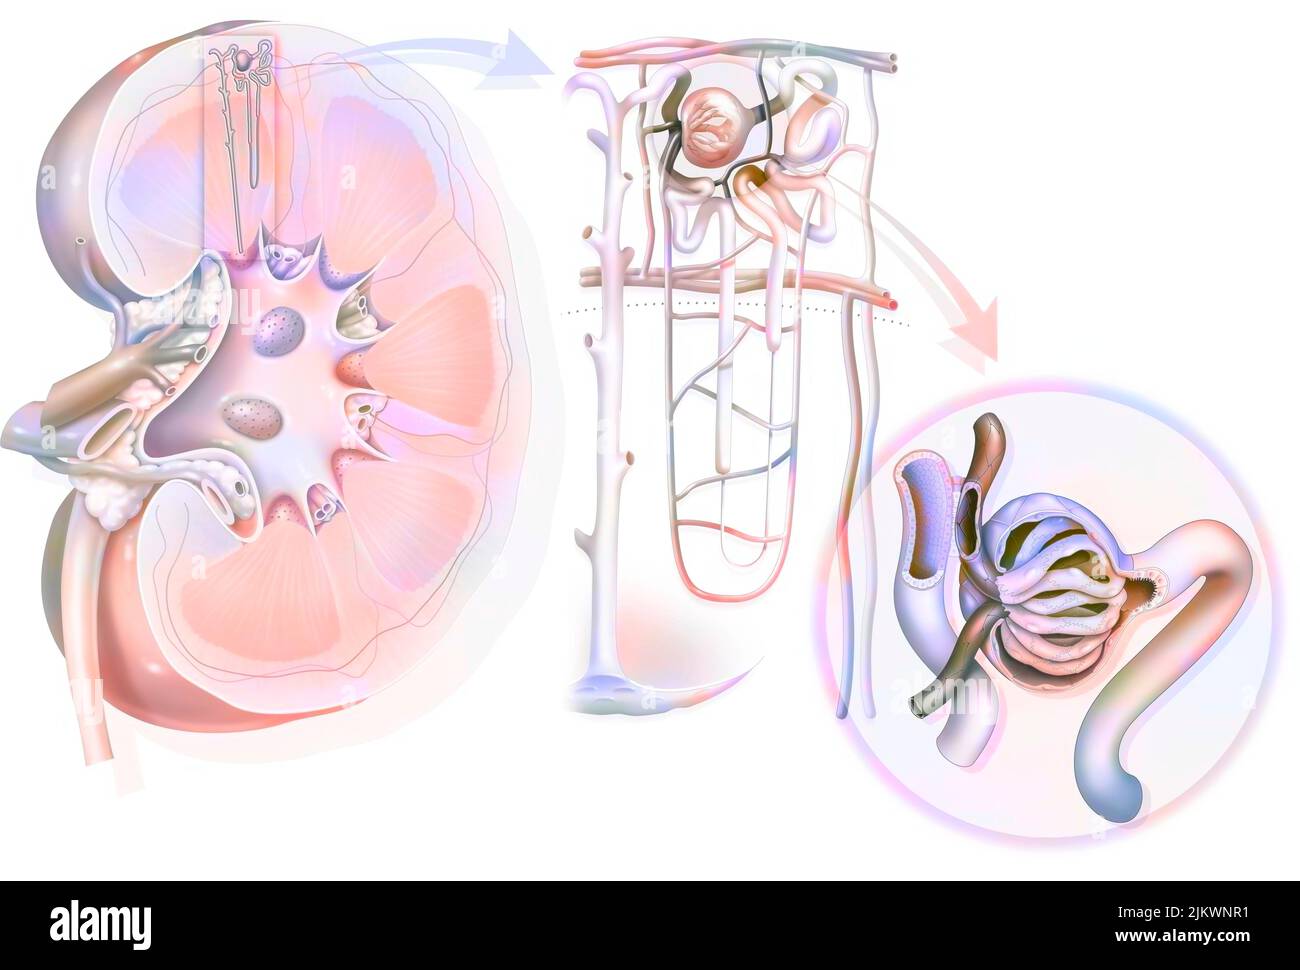

RM2WWBCW9–Reins en vue antérieure avec uretères surrénaliennes et artères et veines rénales. Le rein gauche est placé plus haut que le rein droit.